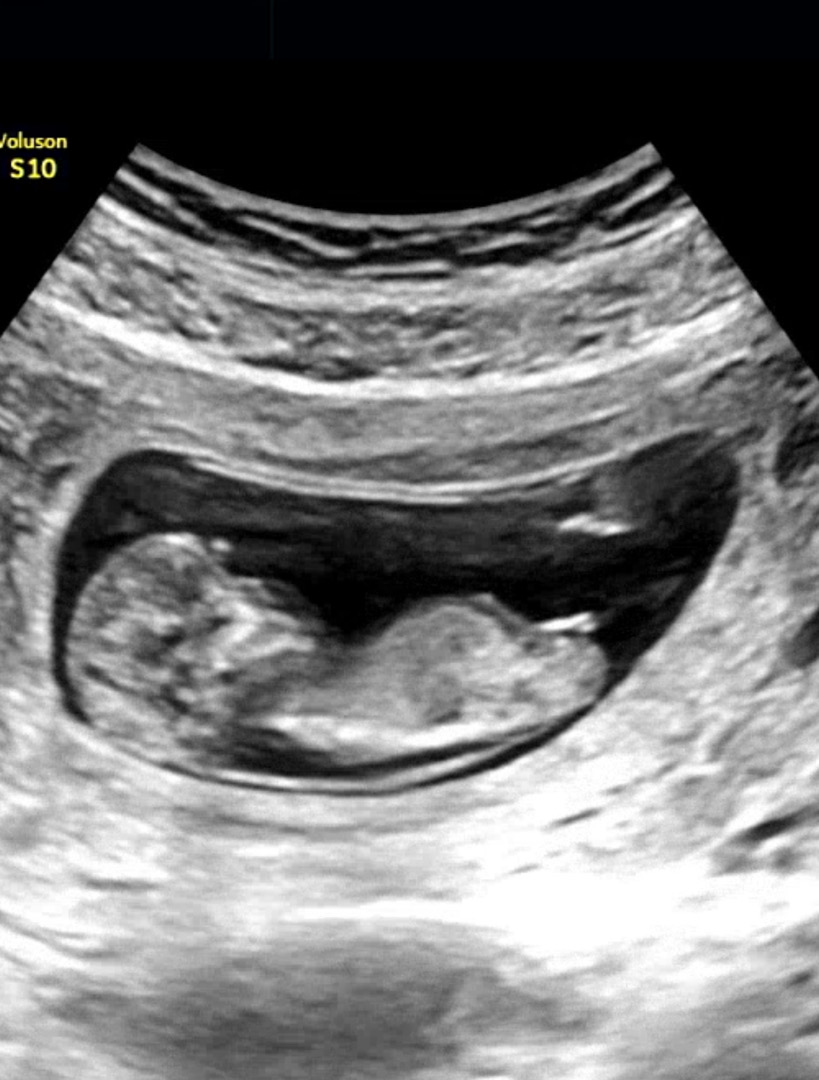

각도법 고수님들 투표해주세요❤️❤️

오른쪽에 보이는게 생식기 맞을까요 ㅠ